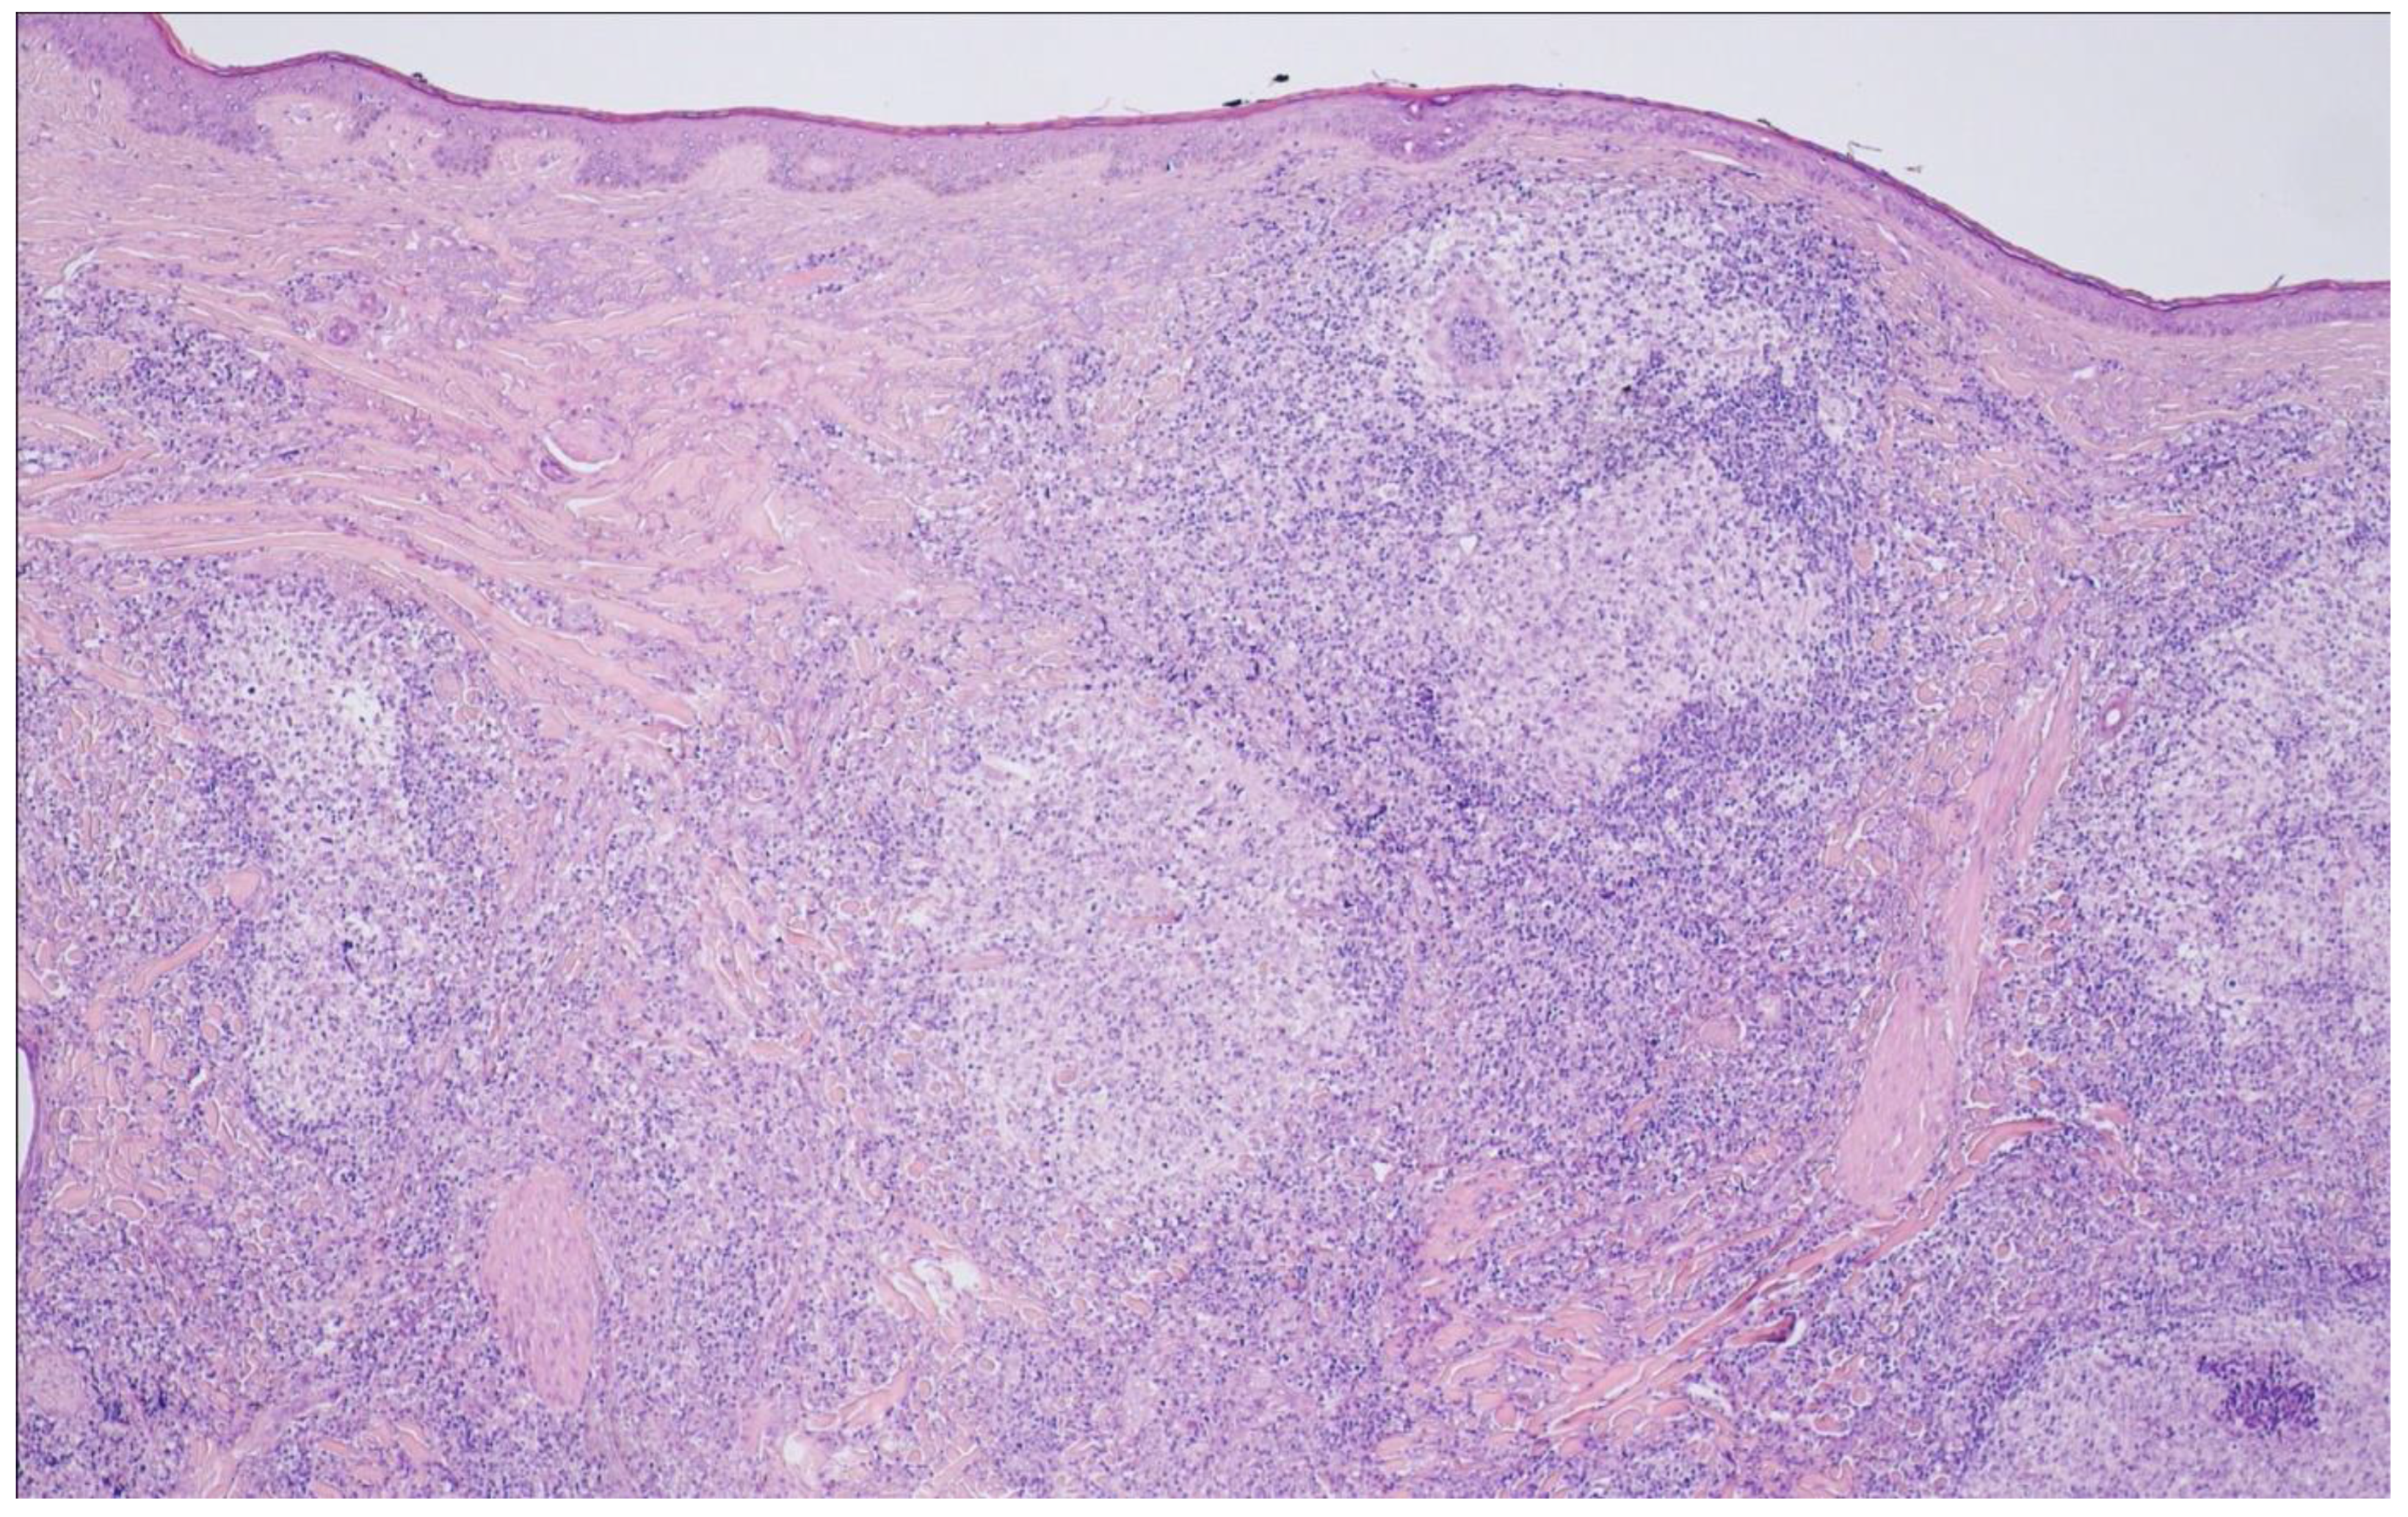

10. Primary Cutaneous Follicle Center Lymphoma